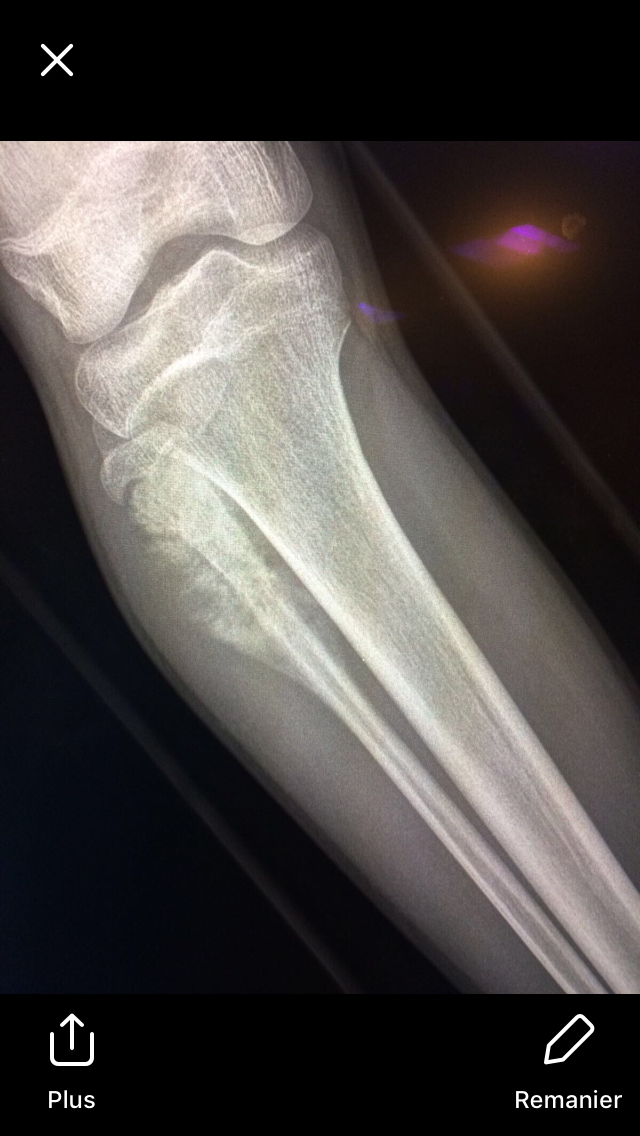

Adolescent présentant une boiterie d’esquive depuis 1 mois.

Chute au football avec réception sur le genou il y a 4 mois, sans complication.

Clinique : tuméfaction en regard de la zone pathologique, pas d’AEG.

Biologie : pas de syndrome inflammatoire.